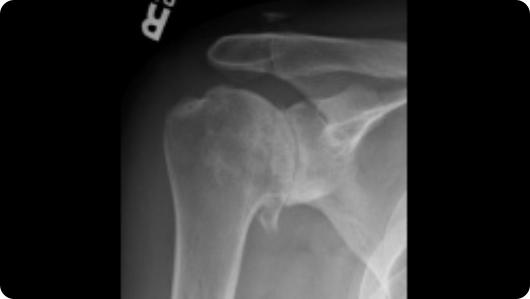

Radiographic image of shoulder arthritis Radiographic image of a total shoulder replacement

Shoulder Arthritis

Total Shoulder Replacement